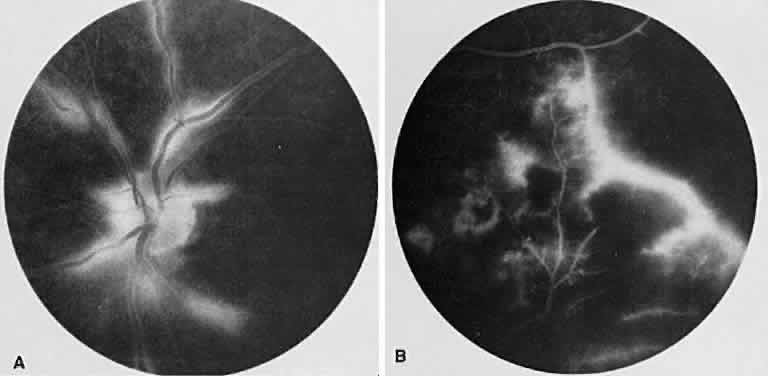

Vogt-Koyanagi-Harada syndrome, also known as uveomeningoencephalitis syndrome, is a systemic disease often found in young, darkly pigmented whites, blacks, native Indians, Hispanics, and Asians. It presents as an anterior and posterior uveitis with disc hyperemia, disc edema, and exudative retinal detachment (Figs. 2A and B and 3A). Systemic signs and symptoms include headache, hearing loss, poliosis, vitiligo, nuchal rigidity, seizures, and even coma. SRNV and disciform scars are late complications. The differential diagnosis should include AMPPPE and sympathetic ophthalmia.

Fig. 2. Vogt-Koyanagi-Harada syndrome. (A) Fundus photograph of the right eye and (B) the left eye showing bullous retinal detachments. (C) Fluorescein angiogram showing multiple hyperfluorescent leaks at the level of the retinal pigment epithelium. (D) Multiple coalescing leaks and fluorescein staining of the subretinal fluid. Large areas of hyperfluorescence involving the entire right posterior pole due to pooling of dye beneath the subretinal space.

Fig. 3. Vogt-Koyanagi-Harada syndrome. A. Fundus photograph of the left eye showing multifocal serous retinal detachment. B. Late fluorescein angiogram showing pooling of dye in the areas of serous detachment. C. Indocyanine angiography showing areas of blocked fluorescence corresponding to serous detachment. More areas of hypofluorescence are noted than those observed on fluorescein angiogram.

There is a characteristic fluorescein angiographic appearance in the early phase showing multiple discrete hyperfluorescent dots at the retinal pigment epithelial level that enlarge over time (see Fig. 2C and D). In the late phase, if there is a serous detachment, the fluorescein pools beneath the subretinal space (see Fig. 3B). The edematous disc hyperfluoresces in the late phase. Generally, the retinal vessels are unaffected.7,8 Retinochoroidal anastomoses also have been documented by fluorescein angiography.9

ICG angiography shows multiple hypofluorescent spots in the posterior pole (see Fig. 3C). These spots may coalesce and obscure the filling of large choroidal vessels. When serous retinal detachment develops, the marked hyperfluorescence observed on FA is not as prominently noted in ICG angiography, presumably because of the highly protein-bound nature of ICG. In fact, diffuse late hypofluorescence may be observed in patients with serous retinal detachment.10 Ill-defined areas of hyperfluorescence corresponding to diffuse choroidal staining may be seen in some cases in the late phases of the angiogram. The optic disc may stain with ICG in the acute phase but usually is minimal compared to that observed on FA.